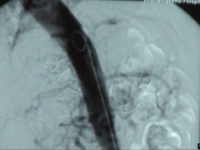

Filmbeispiel: abgangsnaher Verschluss der AMS mit Verschluss des Truncus coeliacus